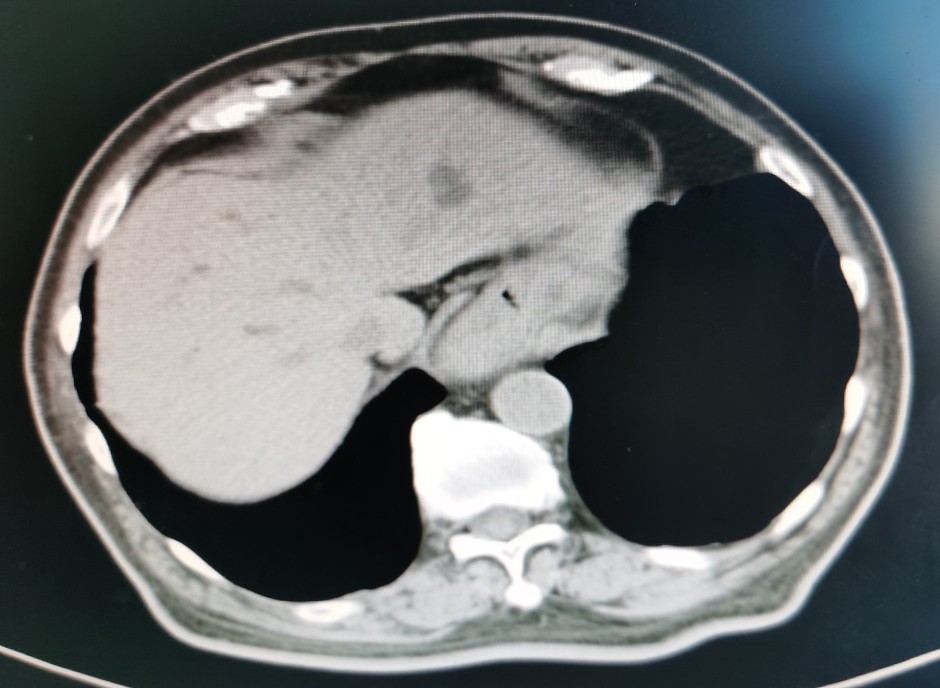

贲门部肿瘤CT表现

尽管病情危重,但王老非常坦然,好像把生死看的很淡,笑看人生总是尽力积极配合治疗。王老尽管年龄很大并且做过好几次手术,但是由于平时保养的不错,看上去偏年轻,并且住院后各种检查发现除心脏功能差一点,其它器官功能还可以。化验检查肿瘤标记物甲胎蛋白(AFP)特别高,超过9000ng/ml,考虑是种特殊类型的贲门癌,血色素63g/l,并且胃管里仍时有鲜血引出,腹部CT检查食管下段及贲门区占位,邻近淋巴结肿大,较上次检查明显增大,考虑为转移。因为病情重,连个增强CT都没敢做。